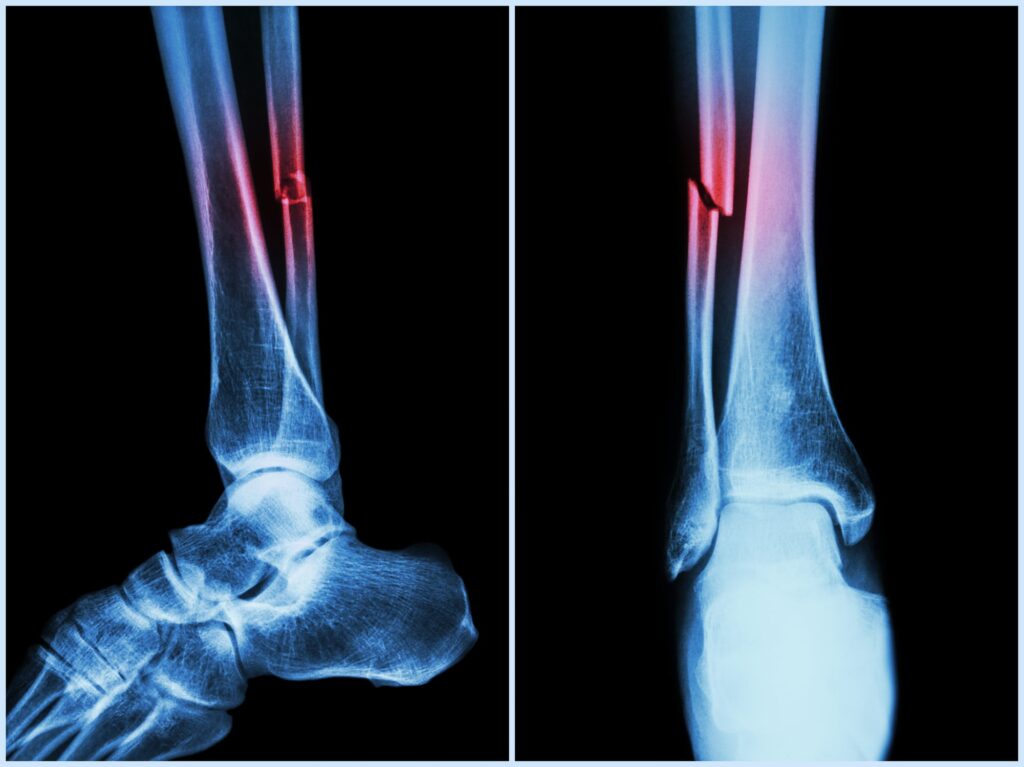

Sprunggelenksfrakturen

Die operative Stabilisierung von Sprunggelenksfrakturen sorgt für eine präzise Ausrichtung der Knochen und ermöglicht eine vollständige Belastbarkeit des Fußes.